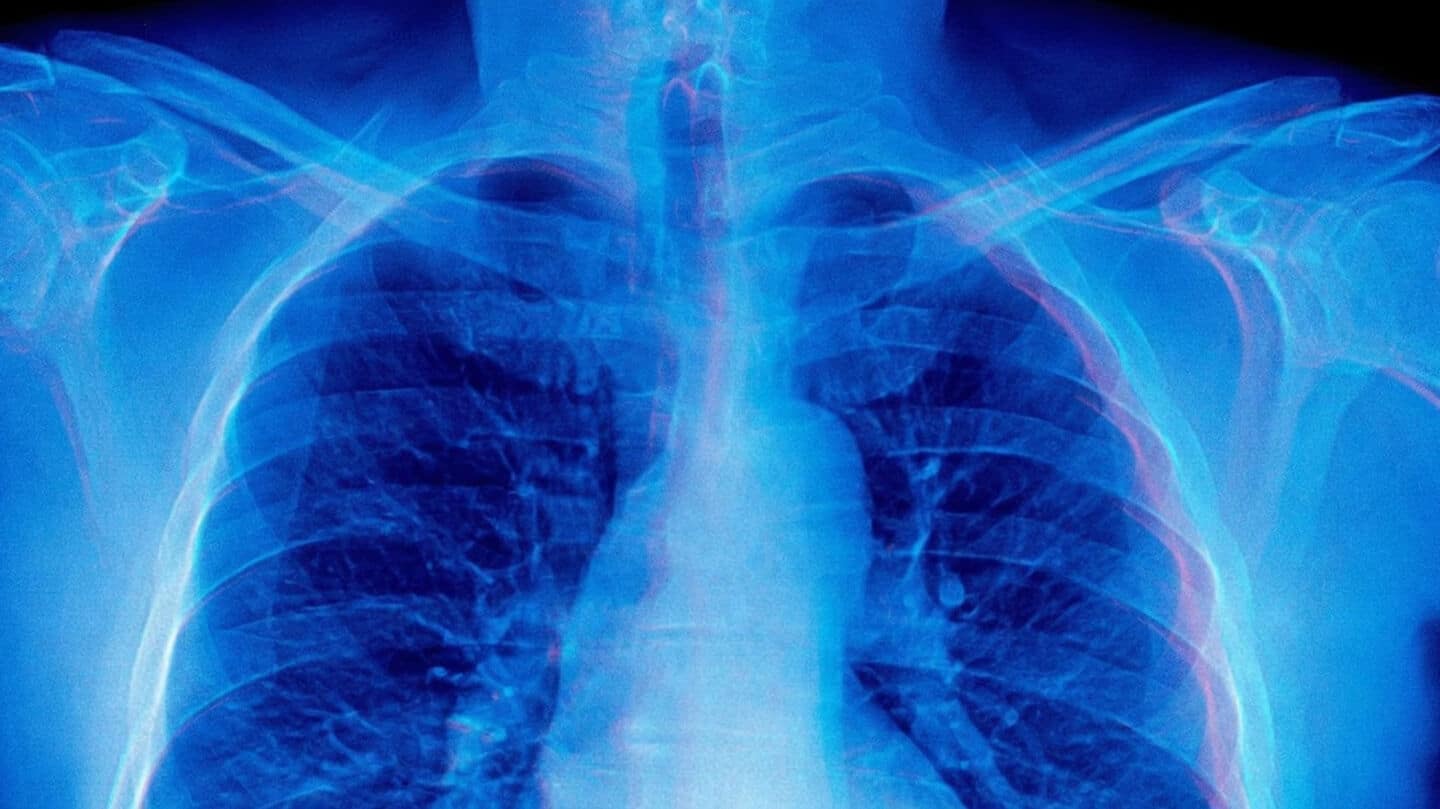

Stanford researchers just found a big flaw in some medical AI models: they can confidently generate detailed image descriptions and clinical findings even when they haven't seen any images at all.

This "mirage reasoning" is kind of like the AI "hallucinations" people have worried about since ChatGPT's early days, and it could be risky if left unchecked in healthcare.